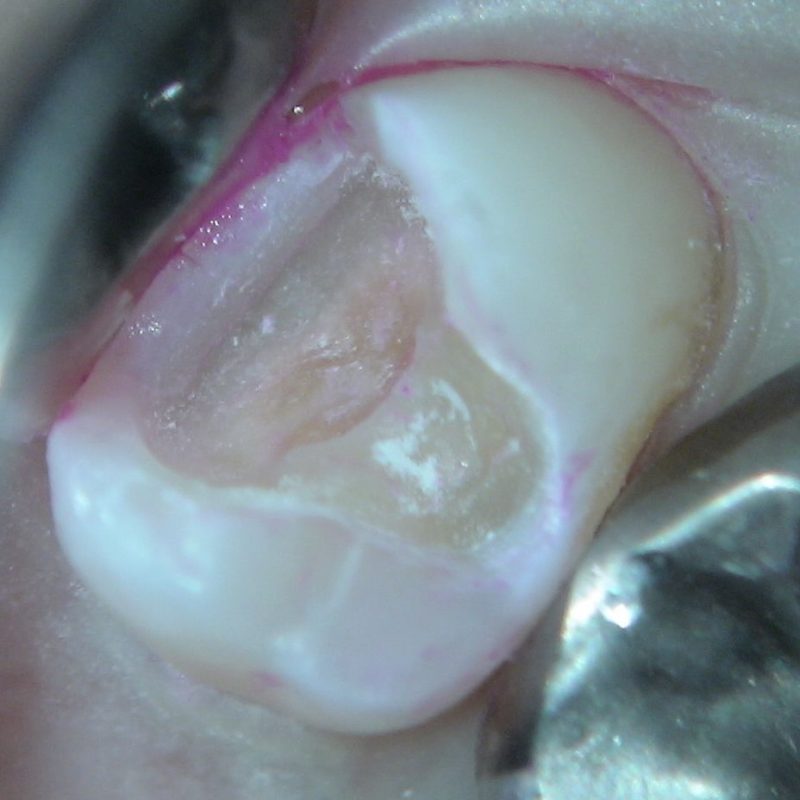

別の症例ですが、 レジンインレーを取り除くと、中に茶色みがかった色の虫歯が認められます。この虫歯の場合相当深くなっていることが予想されます。 |

虫歯を感染に取り除くと、は本来の色になりましたが、神経が露出しそうな状態です。 |

最も神経に近い部分に慎重にPROroot MTAを入れてゆきます。これがうまくいくと、患者さまもほとんど痛みが出ることがありません。 |